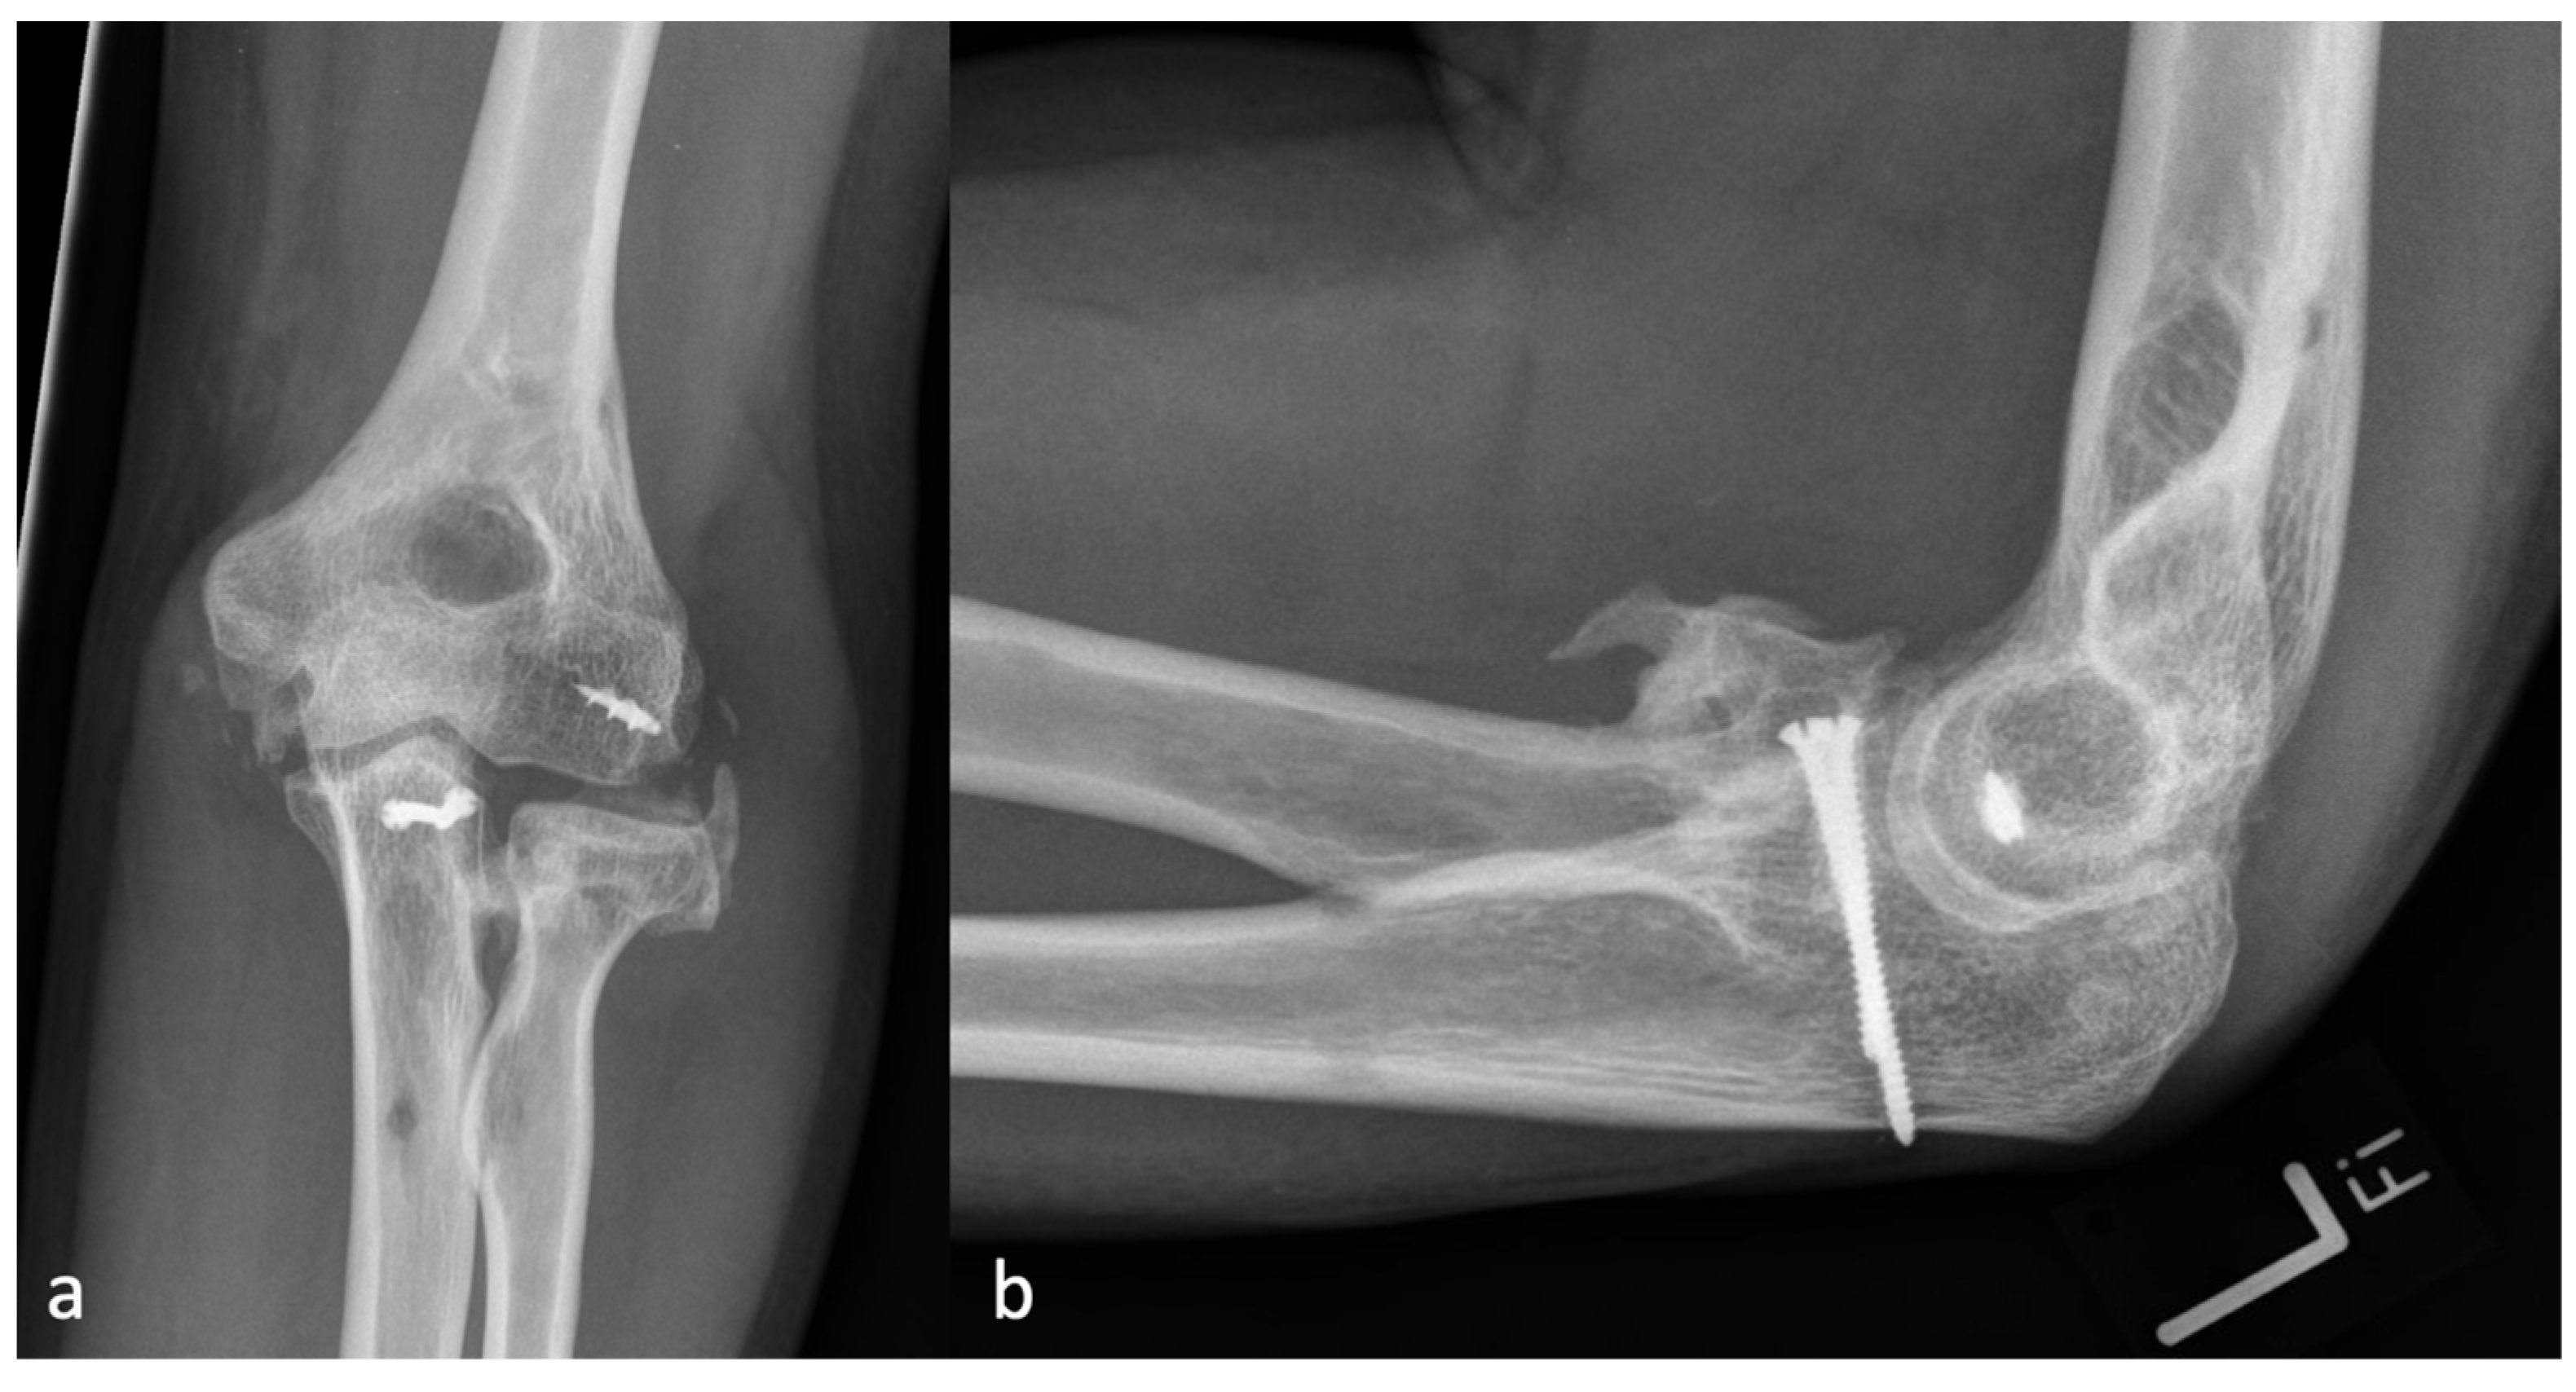

Figure 4.

(a) shows the AP and (b) shows the lateral X-ray with an anterior HO forming a brace from the humerus to the forearm, representing an HO 3a.